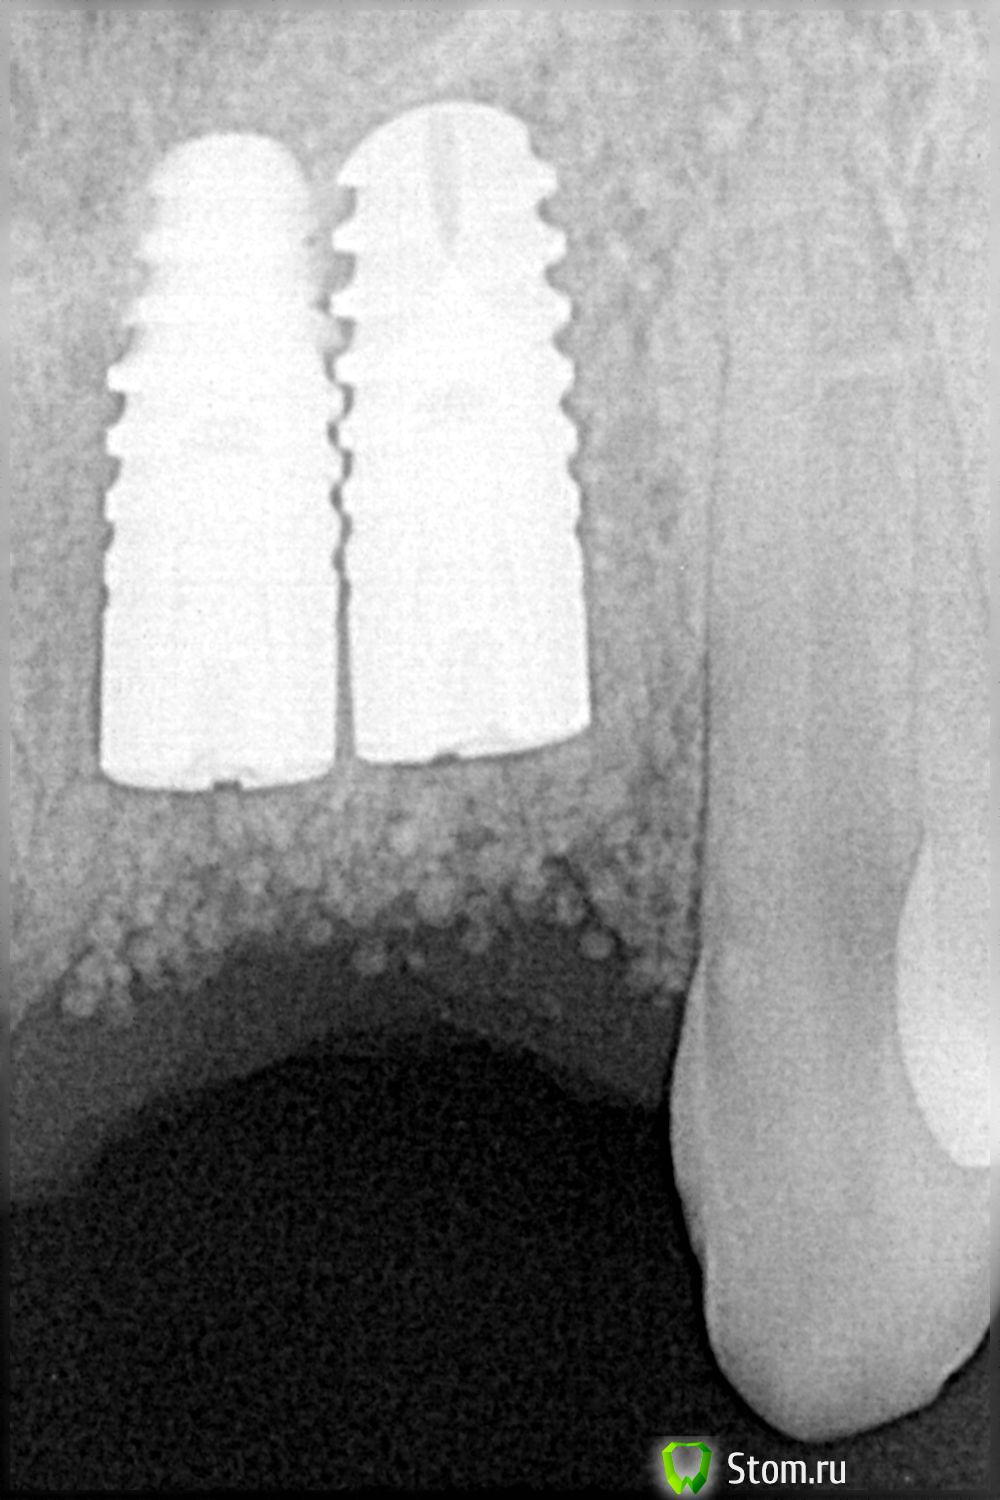

Sib-oboima Опубликовано 19 марта, 2012 Поделиться Опубликовано 19 марта, 2012 Подскажите уважаемые коллеги, у меня возник спор с хирургом, На вопрос- " а не близко ли стоят импланты", мне ответил " нормально". Ваше мнение Ссылка на комментарий

pit Опубликовано 19 марта, 2012 Поделиться Опубликовано 19 марта, 2012 Подскажите уважаемые коллеги, у меня возник спор с хирургом, На вопрос- " а не близко ли стоят импланты", мне ответил " нормально". Ваше мнение По представленным снимкам - близко, но лучше на ОПТГ посмотреть. Скажите, а формирователи десны упиливали? Ссылка на комментарий

Bier Опубликовано 19 марта, 2012 Поделиться Опубликовано 19 марта, 2012 на мой взгляд это называется П. в идеале не менее 3х мм, ну на край 2мм Ссылка на комментарий

Sib-oboima Опубликовано 19 марта, 2012 Автор Поделиться Опубликовано 19 марта, 2012 (изменено) был как-то разговор насчет минимум 3мм, вот что получил , пациент мой знакомый. на мой вопрос а не близко ли к зубу, ответ -3мм ведь же Изменено 19 марта, 2012 пользователем Sib-oboima Ссылка на комментарий

Doc Опубликовано 19 марта, 2012 Поделиться Опубликовано 19 марта, 2012 Прогноз печальный. оставить и делать коронку - означает переделка в лучшем случае сразу после окончания гарантийного срока. В худшем - еще раньше.Снимки с вероятностью 90 процентов не врут.Формирователи рассчитаны на минимально допустимое расстояние между имплантатами при условии параллельной установки, а их пилили. Параллельность здесь более чем достаточная (даже дивергенция небольшая), значит снимки не врут. Ссылка на комментарий

Doc Опубликовано 19 марта, 2012 Поделиться Опубликовано 19 марта, 2012 делайте временную конструкцию (то есть качественную протетику по стоимости временной с возможностью внесения изменений по мере необходимости ..)пациенту честно объясните ,может поймет- в любом случае какое то время конструкцией он будет пользоваться , у меня есть 5 летнее наблюдение за имплантами с 1 мм расстояния, в этом году сделали новую конструкции с учетом потери в десневой части ,поверхности имплантов не оголились ,считаю что повезло и наблюдаю дальше Как вариант это пойдет, конечно, но здесь даже 1 мм нет, здесь резьба аж за резьбу заходит. Трофики никакой, соответственно, не осталось. Что будет с костью в этой ситуации? Так что тезис о плотной работе с хирургом остается в любом варианте... Ссылка на комментарий

Aldo Rain Опубликовано 19 марта, 2012 Поделиться Опубликовано 19 марта, 2012 Видел похожий случай тот же анкилос, имплантаты стоят резьба в резьбу с 2006 года, никаких признаков резорбции, стоят как оловянные солдатики, десна спокойная Ссылка на комментарий